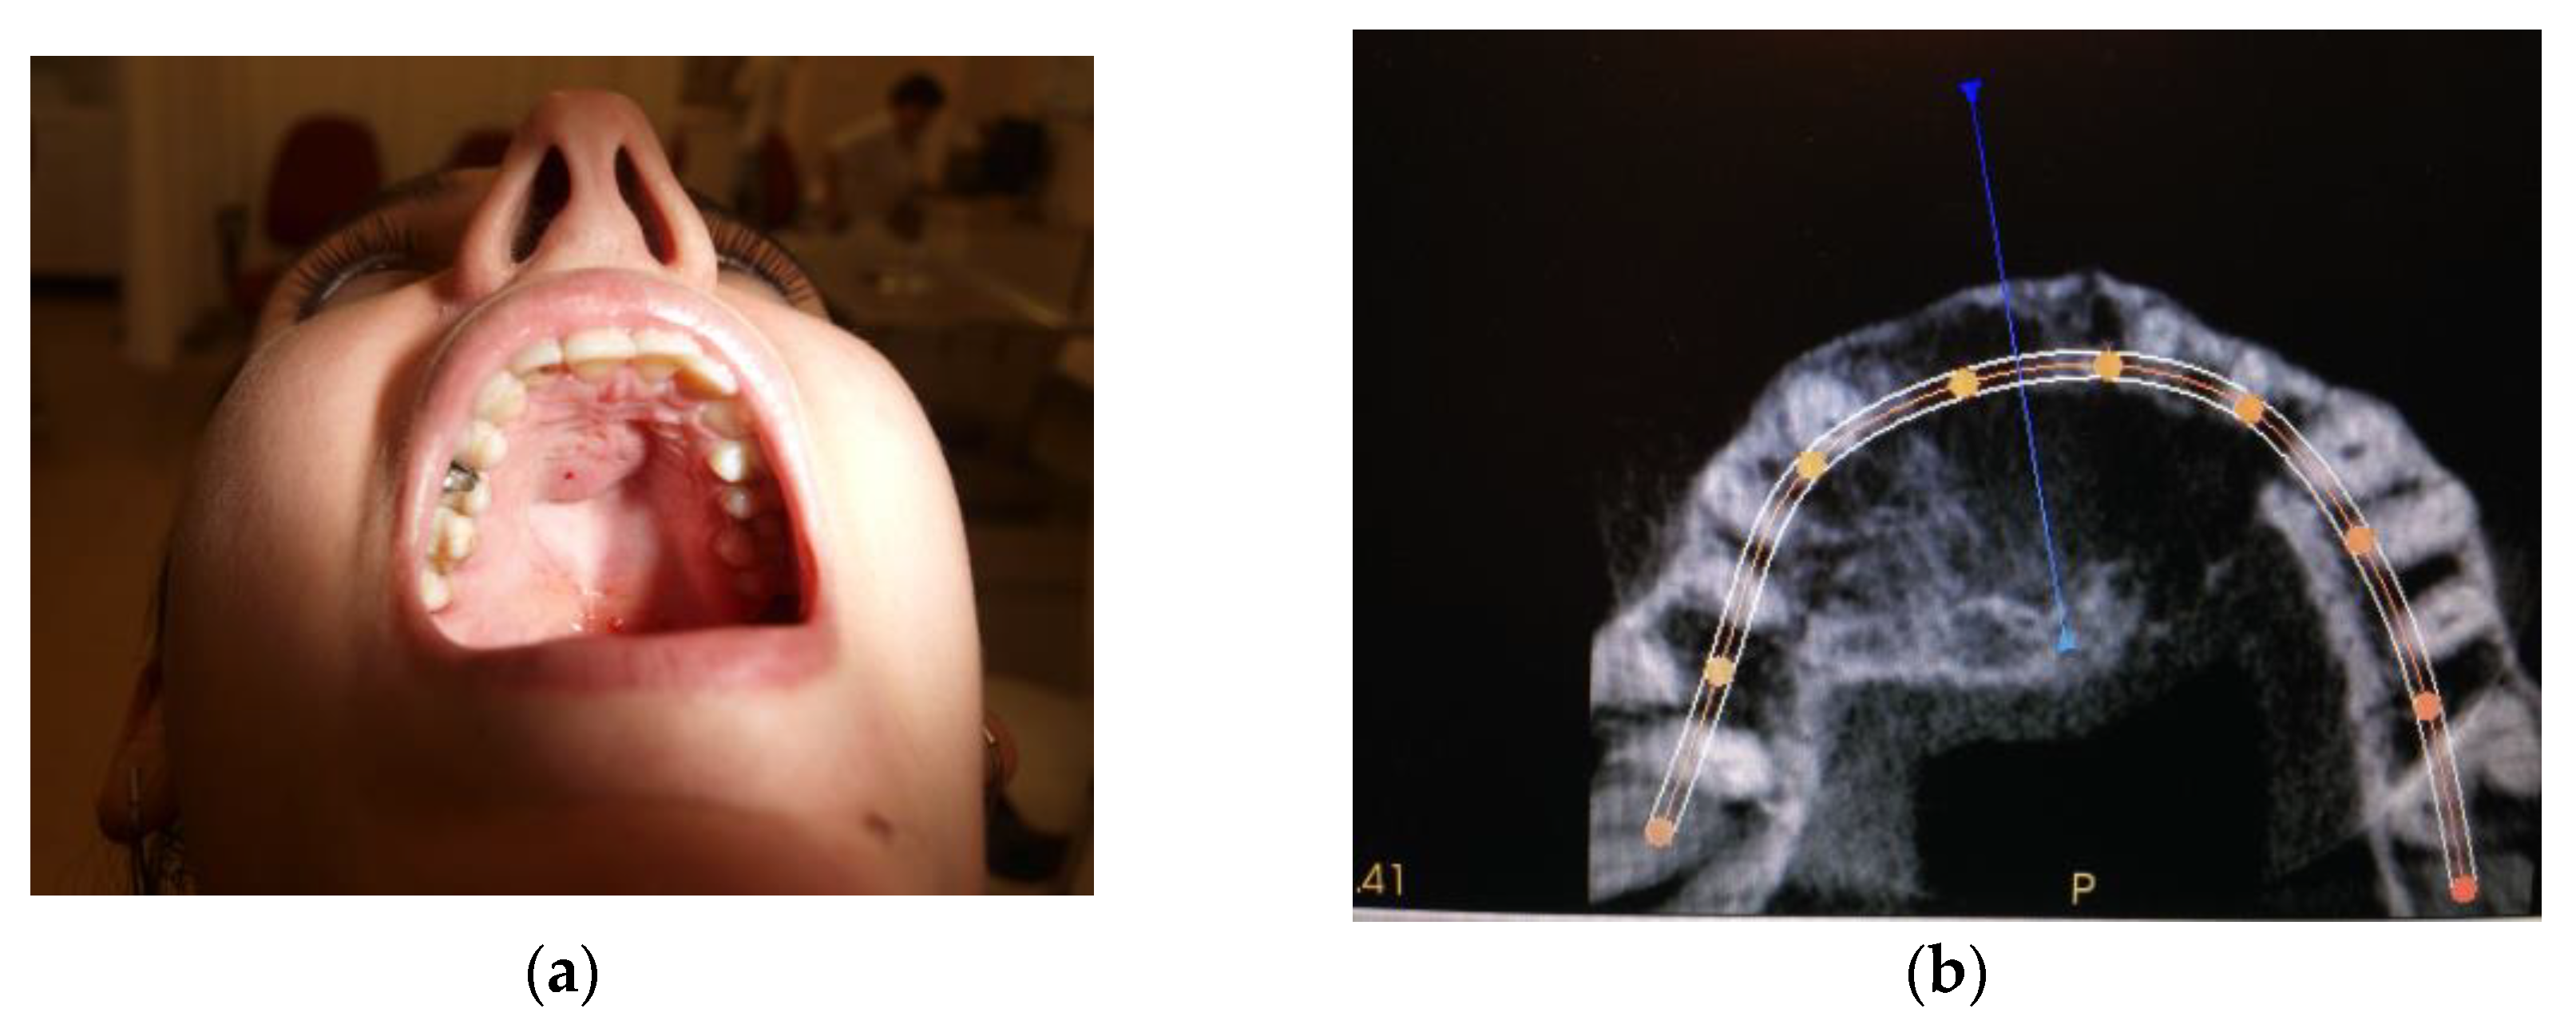

2.2. Case #2

| Case #2 | 29 y.o. | Female | Dexamethasone for 4 months 12 mg/3 mL every week and then 8 mg/12 mL every 2 weeks for the next 3 months | Maxilla | Yes | Success | 8 years |